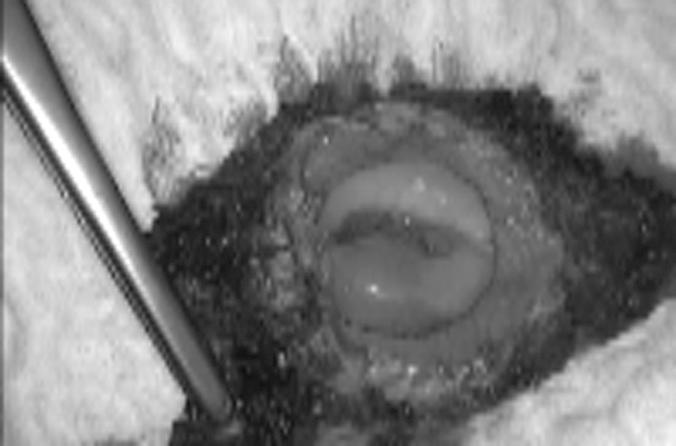

We analyzed 4 patients who underwent laparoscopic radical trachelectomy for early-stage cervical cancer between December 2011 and May 2013.

Four patients were included in this study. Total laparoscopic radical trachelectomy was performed in all cases. The mean age was 26 years (range, 19-32 years), the mean body mass index was 21 (range, 18-23), and the mean length of hospital stay was 33 hours (range, 24-36 hours). The mean operative time was 225 minutes (range, 210-240 minutes), and no complications were reported. During the postoperative period, only 1 patient presented with left vulvar edema, which resolved spontaneously. The pelvic and parametrial lymph nodes, as well as the vaginal cuff and cervical resection margins, were negative for malignancy in all cases. On average, 18 pelvic lymph nodes (range, 15-20) were removed. The tumor stage was IB in all 4 patients, and the mean tumor size was 17 mm (range, 12-31 mm). No patient required conversion to laparotomy.